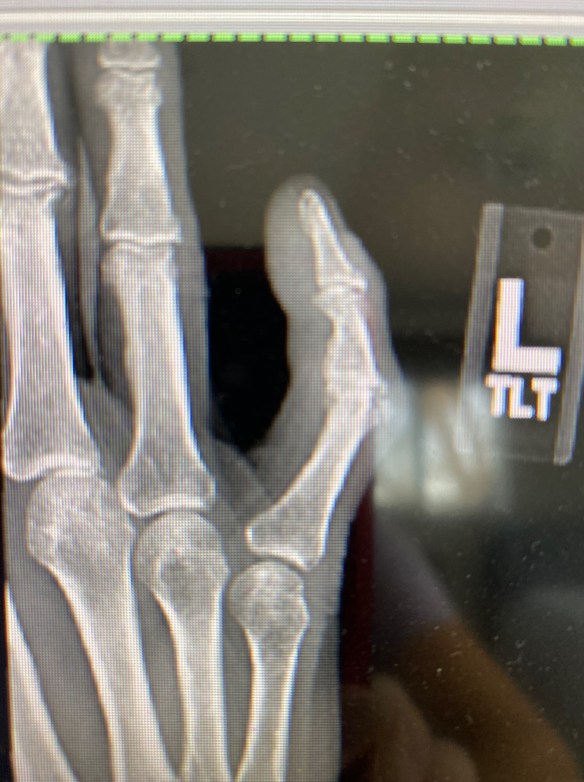

I broke the knuckle straight across and knocked a chip out of it.

This time I knocked the little joint out of place

Arthritis has taken over the first knuckle and will take over the tiny knuckle at the tip.

Ouch. That x-ray even LOOKS painful. I hope that finger isn’t “whispering” too loudly.